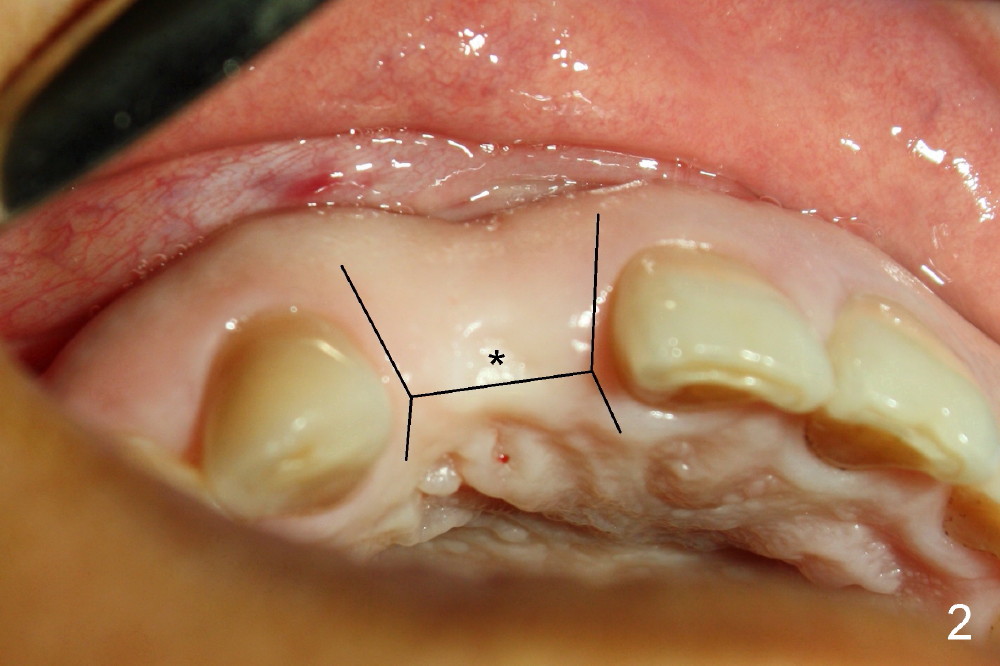

To increase buccal soft tissue bulk, the transverse incision is made lingual to the original socket (Fig.2 *). When the flaps are raised, the alveolar ridge appears to be deviated buccally; the implant (3.8x14 mm, insertion torque ~ 35 Ncm) also looks to be tilted too buccally even though it is placed in the middle of the ridge (Fig.3). An angled abutment (3.9 mm, 25º, 2 mm cuff, Torx A) has been adjusted buccally (Fig.4). The immediate provisional looks long (Fig.5). When the buccal flap is modified (Fig.5 insert) and sutured (Fig.6), the provisional looks to be tilted buccally. A custom Zirconium abutment should be used later on. All of these difficulties are due to delayed implantation with bone atrophy and are avoidable using immediate implant technique. Or check occlusion at the initial stage of osteotomy.